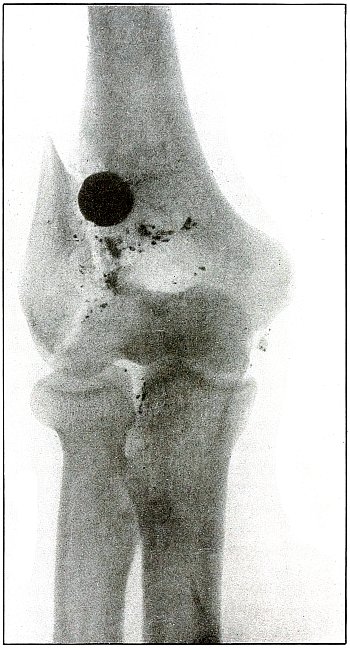

Plate 55.

_

[Pg 121]

Rifle—Plate 55.

LOWER EXTREMITY.

Gunshot Fracture of the Lower Third of the Shaft of the Femur.

The course of the bullet was diagonally anteroposterior, with a velocity near mid range, without causing much displacement of fragments.

The wound of entrance and exit would be almost the same in appearance.

Treatment and results would be similar to case shown on plate 54. Many of these wounds are infected, due, no doubt, to the difficulties of arranging a clean first-aid dressing and effecting satisfactory immobilization during the first stage of transportation.

Infection from clothing carried into the wound is rare, as the fairly high velocity of the bullet causes a spreading of the fibers without division or punched-out section before the bullet.

As a rule the infected cases of this class recovered without loss of limb. Amputation was very rare. [Pg 122]